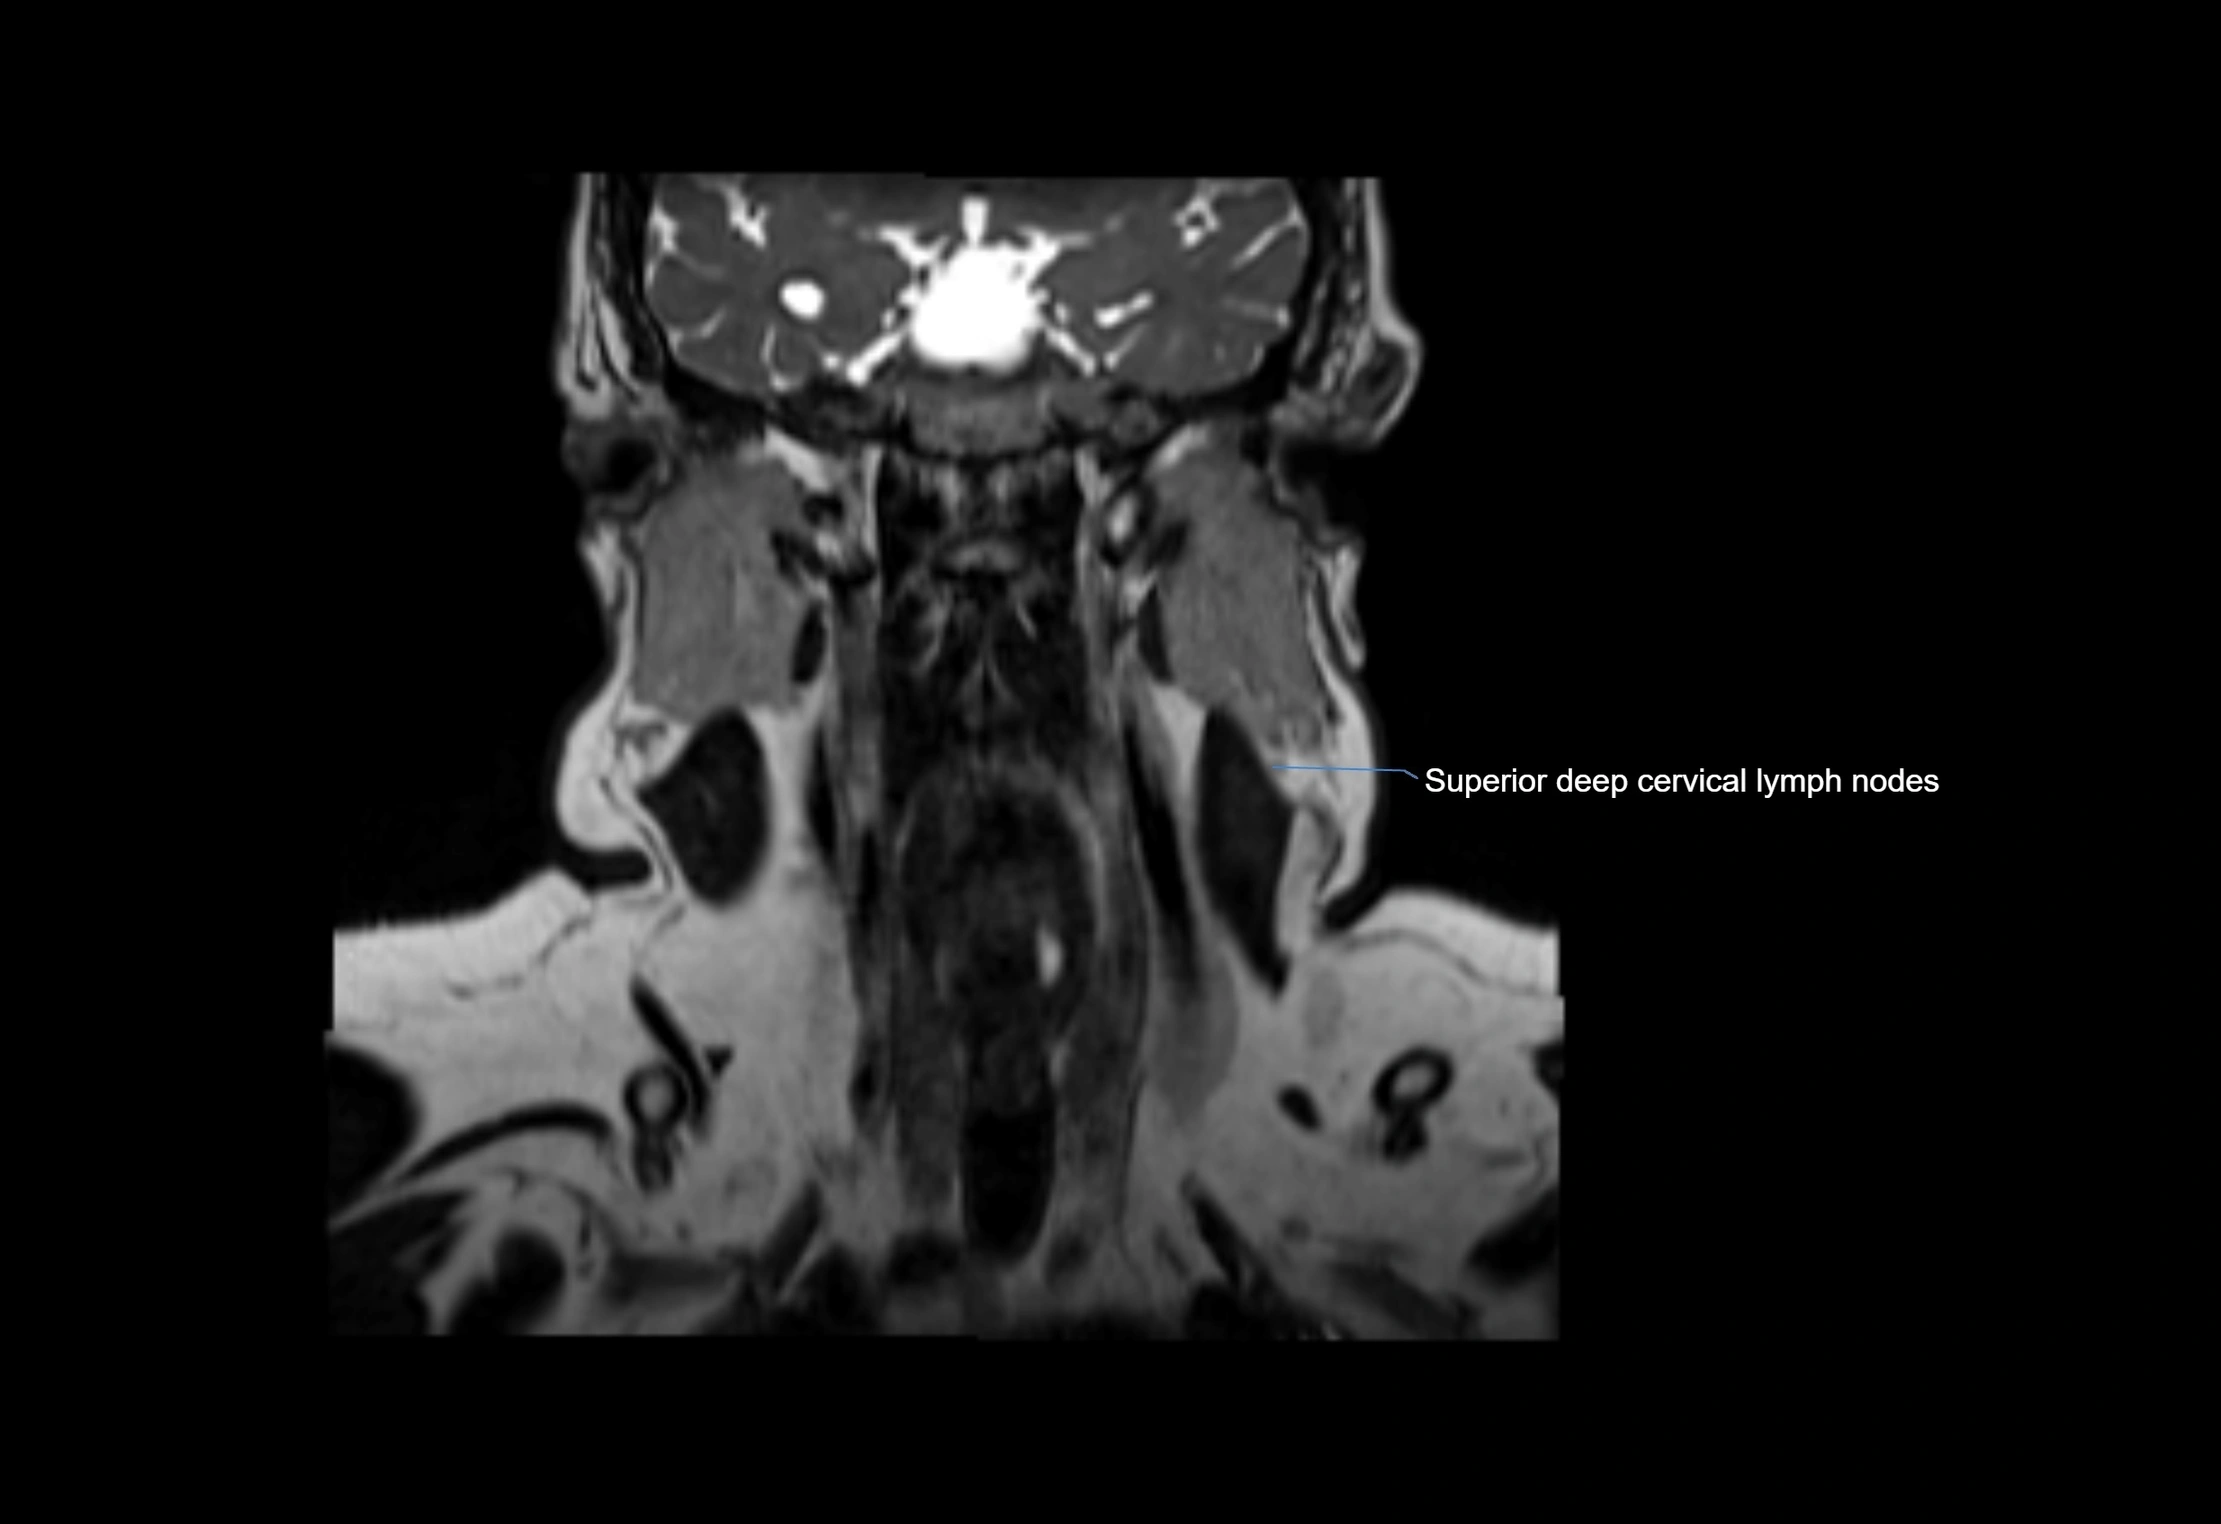

MRI Appearance

T1-weighted images:

• Normal accessory nodes appear as small, oval hypointense to intermediate signal structures within subcutaneous fat

• Surrounded by hyperintense fat, enhancing contrast for visualization

• Pathological nodes may appear enlarged or rounded, sometimes with cortical thickening

T2-weighted images:

• Nodes show intermediate signal, with surrounding fat bright

• Useful for detecting edema, inflammation, or infiltration

• Fatty hilum may appear slightly hyperintense relative to cortex

MRI images

image